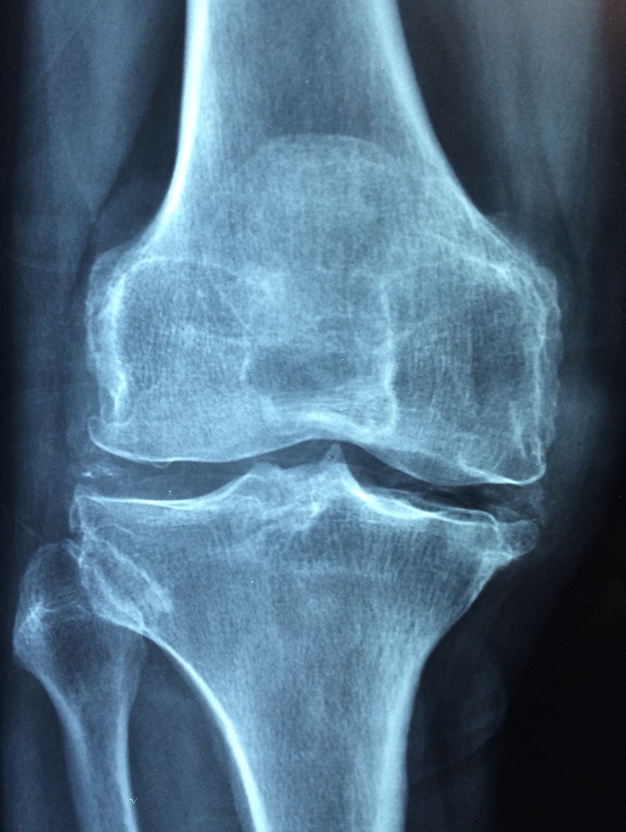

골다공증 증상과 진단 수치

골다공증의 주요 증상은 뼈의 약화로 인한 골절이며, 일반적으로 척추, 고관절, 손목 등에서 골절이 발생할 수 있습니다.

또한 등, 허리 통증이나 자세의 변화(구부정한 자세), 신장이 줄어드는 현상이 나타날 수 있습니다.

골다공증은 골밀도 검사(BMD, Bone Mineral Density)로 진단하며, T-점수가 -2.5 이하일 경우 골다공증으로 진단됩니다.

T-점수가 -1.0에서 -2.5 사이인 경우는 골감소증(골다공증 전단계)으로 분류됩니다.